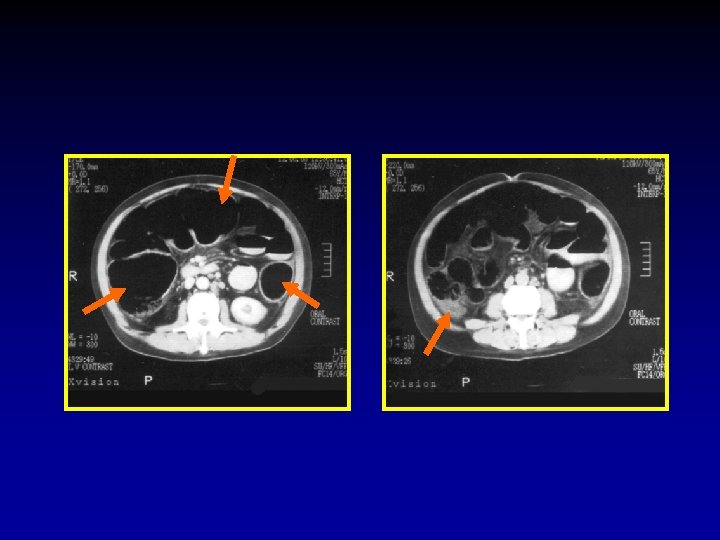

The CT signs of closed loop obstruction of the small intestine are: 1. Evidence of small bowel obstruction. 2. A U-Shaped or radial configuration of the fluid filled dilated loops. 3. At the site of obstruction, a whirl sign, beak sign, triangular loop, or two adjacent collapsed loops.

A At U-Shaped the site Evidence of configuration obstruction of. The small Whirl of two bowel theadjacent sign fluid obstruction. filled collapsed dilatedloops